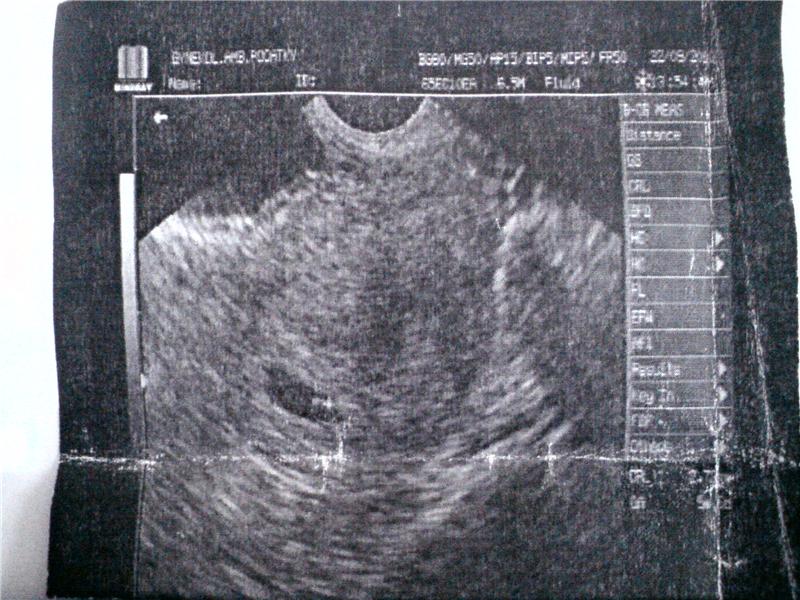

mufik 5+6tt.